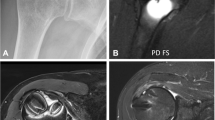

In Fig. 11, a montage is presented for visual comparison among the three assessment tools.

Animal from group 2 weeks selected for visual comparison among the three assessment tools. a Coronal slice of DCE-MRI. Highlighted in green is the right defect, which was filled with an autogenous bone; in red, the left defect, filled with blood; in orange, an ROI of the brain, and in yellow, one of the masseter muscle, which was used as references to normalize the IAUC140 values for both defects; b a bird’s view of the right and c left defects on μ-CT. d A coronal slice of the right and e left defects on μ-CT. f A ×2 magnification of a slide containing both defects, stained with toluidine blue; g a close-up of the right and h left defects